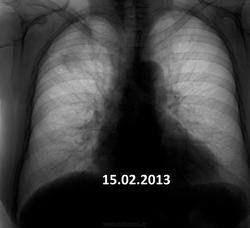

Пожилая опрятная женщина, жалоб нет, просит "отпустить". В феврале фтизиатры написали пневмонию. Сжалился - написал что-то вроде плеврофибрознотакая-то хрень.

Коли фтизиатры отпустили так на них и грех.Сопоставляя с архивом от туберкулёза не отмахнёшся.

Но ведь не может туберкулез меделенно развиваться 4 года?

имеет место. Томографировать надо обязательно.

Не надо сбрасывать со счетов и левую верхушку.

Очень даже может.

Увы! Мне кажется - справа имеет место рецидив. Валентин Львович не зря на левую верхушку обратил внимание.

На первом месте- Tbc.

На втором: Если в легком неясная картина - ищи БАР.

В любом случае ТМГ.

+1. Не пневмония это точно. Прогресс слишком долгий. Больше склоняюсь к онко.

Я за онкологию